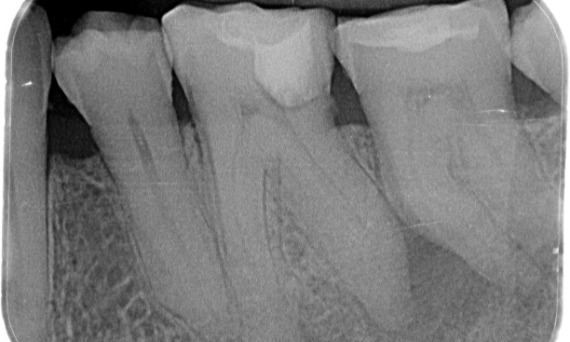

Avant : Une lésion carieuse a été observée sur la première molaire inférieure droite. L’examen radiographique a révélé la proximité de la lésion avec la corne pulpaire et, en l’associant au motif de la consultation, on a conclu qu’il s’agissait d’une pulpite chronique irréversible.

Après : La cavité d’accès a été réalisée de façon aussi prudente que possible. La solution TruNatomy a été choisie en raison de l’âge du jeune patient. Nous devions préserver la dentine autant que possible afin d’augmenter la capacité de la dent à surmonter la charge occlusale et d’accroître la longévité de la restauration finale.